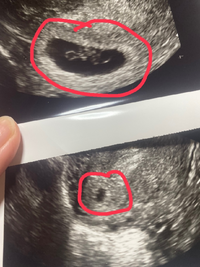

妊娠2ヶ月 (妊娠6週目):心拍確認! まだ微妙な出血は続いていますが、とりあえず検診に。 なんとなく体は少し軽くなった感じ。 駅くらいまでなら歩けそう。 ってことで、普通に電車に乗って検診へ。 子宮口にあるポリープからの出血はなさそう妊娠6週ころの超音波写真 心拍が確認できることもあります 小さな豆粒の赤ちゃん(胎芽)が細長く成長してきます。 心拍を確認できることもありますが、まだ微弱です。 超音波写真では豆粒ですが、実際は目や口、手、足のもとがつくられています 6週だと心拍確認できないこともありますよ。 6週目で胎嚢確認、心拍ナシ。 7週目も同じだった時、医師から流産の可能性が少なからずあると

妊婦 7 週目で心拍が確認できましたが、 122 回 / 分と書かれてました。 7 週目だと最低でも 140 回 / 分だと聞いたのですが、、、 心臓が止まり、流産の可能性はありますか? Q. 4 現在、妊娠 9 週目ですが、先日の診察で胎児の心拍数が高いと言われ心配し妊娠週 6w1d 排卵日が特定できているので、確実に6w1dのエコーです (^^)元気な心拍と2mmの赤ちゃんが確認できました! 2人目の妊娠なので、まだ1歳10ヶ月の長男を抱っこしたり追いかけ回したりでゆっくりできないので、赤ちゃんが心配ですが生命力を信じて 妊娠6週で胎嚢が見えない、7週でも心拍が確認できなかった話 01 検査薬陽性 02 産婦人科受診 04 無事胎嚢確認 05 妊娠9週目の検診でやっと心拍確認

こんにちは!ぽっくる(@2525pokkuru) です。初マタ、現在14週と4日です。 前回に続き、 妊娠6週目・7週目・8週目の個人的な症状 をまとめていきます! この3週間は、つわり本格化 そして病院調べや心拍確認、仕事の調整など、 1番心身ともに忙しかった時期 です(泣) 心拍は何週目に確認できましたか? 妊娠初期の妊娠の大まかな目安は8週までに胎児心拍が認められることです。 そのため、 妊娠検薬で早めに妊娠がわかったとしても、 その後心拍確認まで何度も病院に足を運ぶことになります。 およそ1週間ごとに診察 くろみつさんの妊娠6週目のエコー写真 心臓の動きが確認できてひと安心 エコー画像で振り返る、私に宿った小さな命が大きく育って誕生するまでの記録 おなかの赤ちゃんは元気でいるのかどうか不安だった2週間を経て、やっと検診の日が来ました